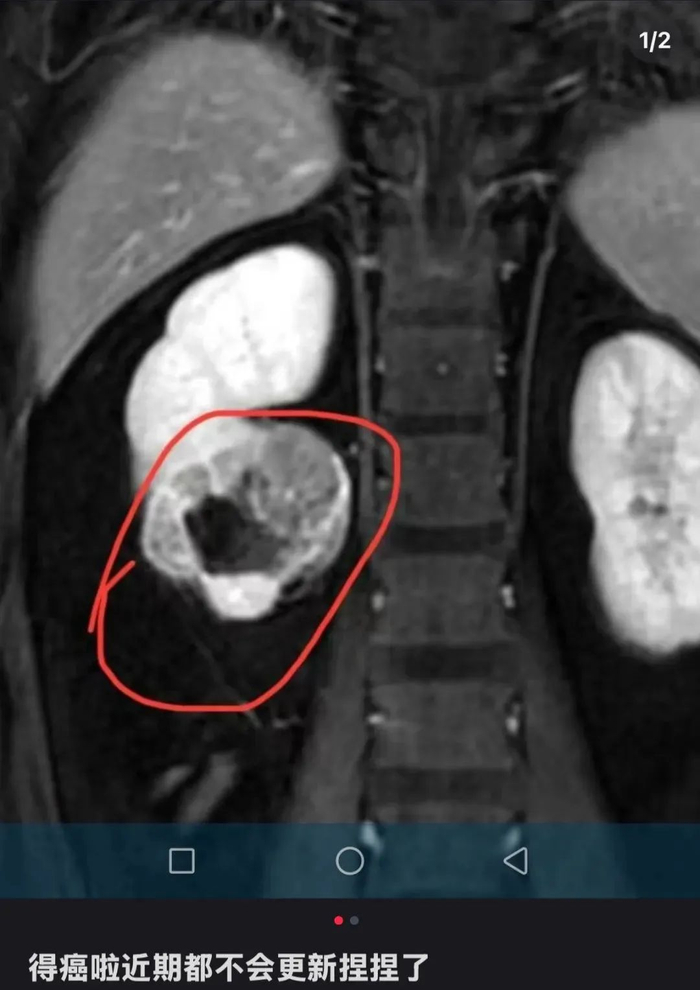

近两年,一种装在透明袋子里的“捏捏”,成为年轻人缓解压力的热门选择。近日,一位ID名为“有只猫叫小朋友”的捏捏博主发文告诉粉丝:“得癌了,近期都不会更新捏捏了。”博主公开了自己的诊断病例,显示诊断意见为“右肾下级占位,肾CA可能,建议穿刺活检。”意味着医院给出的诊断是右肾下极区域出现异常组织占据,存在肾细胞癌的可能,让解压玩具捏捏致病问题,再度成为热议话题。